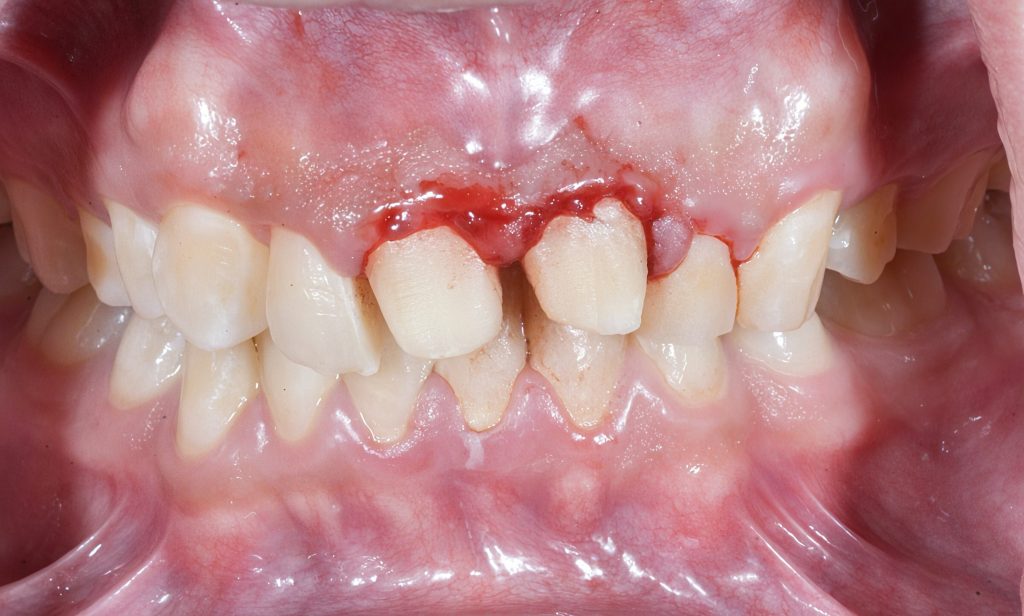

A patient presented with discoloration and loss of vitality of both maxillary central incisors following previous trauma. Pulp necrosis with periapical rarefaction was diagnosed. Endodontic therapy was performed under rubber-dam isolation and high-magnification control. The canals were shaped conservatively and obturated using the warm vertical compaction technique, ensuring dense 3-D filling and preservation of pericervical dentin.

Diagnosis: Pulp necrosis secondary to trauma

Treatment Objective: Maintain maximum dentin integrity and establish a hermetic apical seal before final esthetic rehabilitation